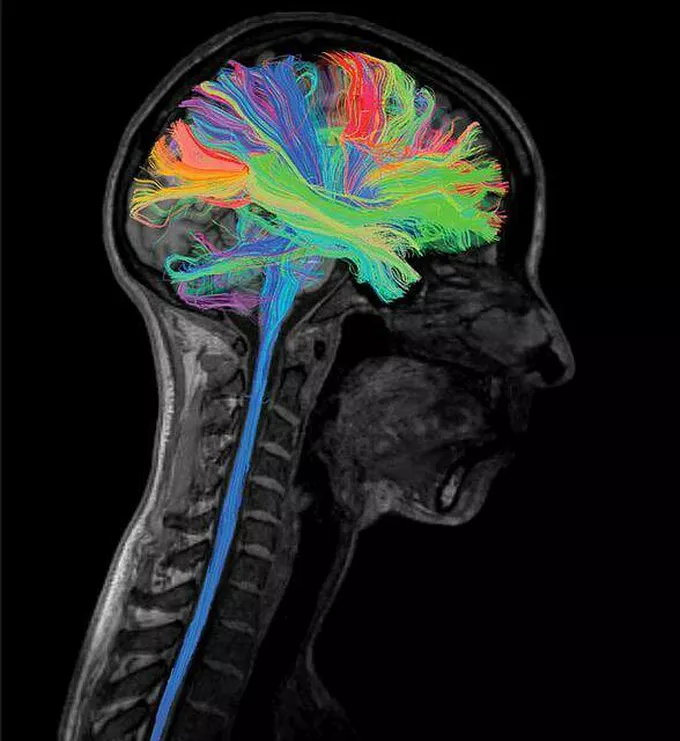

Diffusion Tensor Imaging (DTI)

A type of MRI that maps the diffusion of water molecules in the brain, allowing visualization of white matter tracts and connectivity.